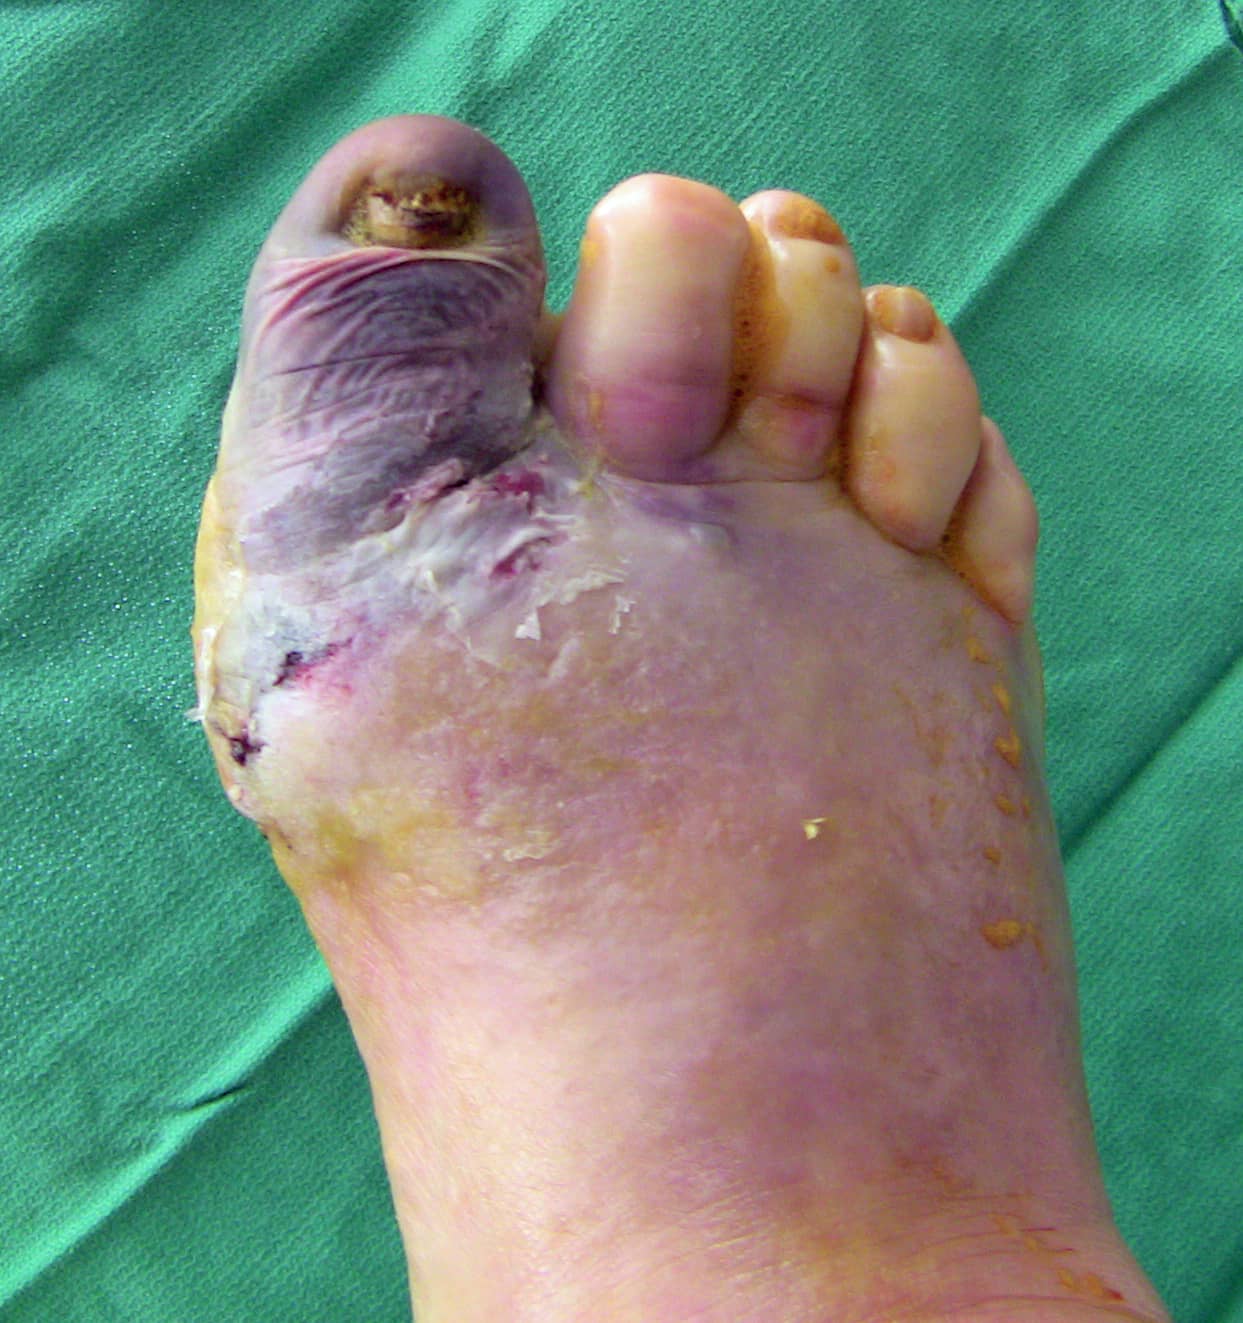

- Sin embargo, el mayor problema del pie de Charcot es que las deformidades pueden crear zonas con prominencias óseas debajo de la piel (el hueso se ubica justo debajo de la superficie de la piel). Esto provoca úlceras o lesiones que surgen del exceso de presión en la piel. Una vez que la piel se abre, el riesgo de desarrollar una infección en el pie es muy alto y, debido a la irrigación sanguínea deficiente, los diabéticos tienen dificultades para combatir las infecciones y curar las heridas. Por este motivo, los diabéticos con pie de Charcot tienen un 50 % de probabilidades de terminar con una amputación si desarrollan una úlcera, frente a solo el 10 % de probabilidades sin una úlcera.

- Desbridamiento de úlceras. Las úlceras pueden requerir la ayuda de una cirugía para poder sanar. Desbridamiento simplemente significa limpiar la úlcera y quitar las partes muertas de la piel que posiblemente no sanen. Puede colocarse un yeso después del desbridamiento para quitar la presión de la úlcera a medida que sana.

- Extirpación de las prominencias óseas (exostectomía). Las deformidades pueden provocar prominencias óseas debajo de la piel, y la presión sobre la piel causada por esos huesos puede provocar úlceras. La forma más simple de evitar que una prominencia ósea cause una úlcera es quitando ese fragmento de hueso. Las prominencias en la parte inferior y medial del pie son muy propensas a causar úlceras.